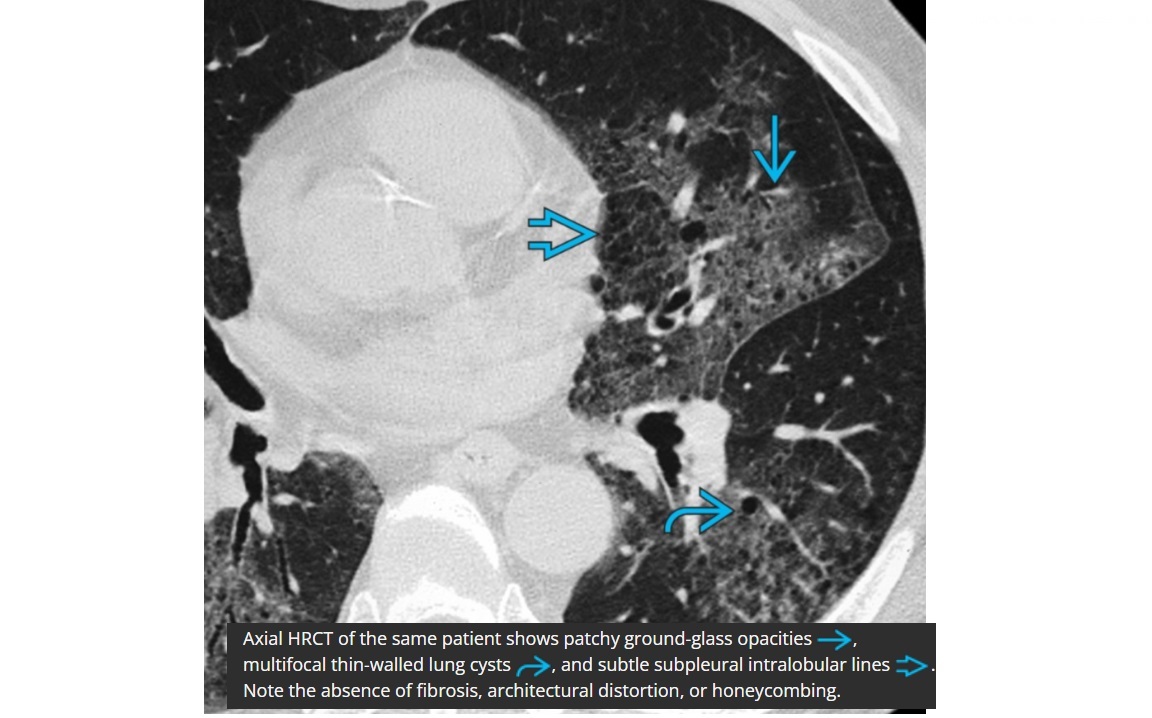

DIP

Smoker

Bilateral, lower zone predominant ground-glass opacities

± subpleural **intralobular lines/retiuclations **

Small, round,** thin-walled** (2-4 mm in diameter)

Spectrum/similar HRCT to RB-ILD

+ centrilobular nodules

+ upper lobe predominated